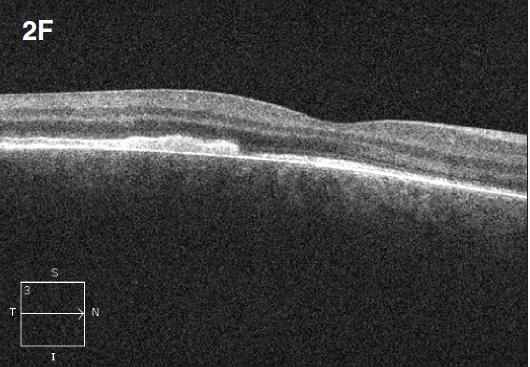

Figure 2. Diffuse choroidal hemangioma. The patient was a nine-year-old boy with history of Sturge-Weber syndrome, referred due to decreased vision (20/200) and subretinal fluid in the right eye. The fundus exam revealed retinal pigment epithelium mottling around the optic nerve with a surrounding cuff of subretinal fluid (A). B-scan ultrasonography demonstrated a solid, highly echogenic lesion, with diffuse choroidal thickening (B). OCT showed subretinal fluid with cystic spaces in the outer retinal layers (C). One year after treatment with external beam radiotherapy (20 Gy in 10 fractions, 2 Gy/fraction), the fundus exam revealed a regressed hemangioma (D). Tumor regression was confirmed by B-scan ultrasonography (E). Concomitant resolution of subretinal fluid was noted on OCT (F). Visual acuity improved to 20/60.

Clinically, diffuse choroidal hemangiomas present as generalized red-orange choroidal thickening, with or without an exudative retinal detachment (Figure 2a). These hemangiomas have been classically described as a “tomato catsup fundus.” There might be areas of excessive thickening, simulating circumscribed choroidal hemangiomas. In some cases, the lesions might be subtle, without welldefined borders, and may involve more than half of the fundus area.

B-scan ultrasonography demonstrates solid, highly echogenic lesions, with diffuse choroidal thickening (Figure 2b), and high internal reflectivity on A-scan. Early hyperfluorescence with persistence of hyperfluorescence through the late phases of the angiogram are seen with fluorescein angiography. Similar findings are observed on ICG, with a characteristic lacy intrinsic vascular pattern, with a diffuse distribution.16 OCT may be used to confirm the presence of subretinal fluid (Figure 2c).